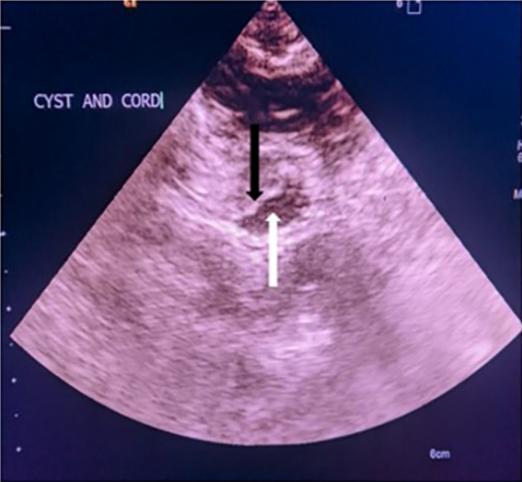

图2、术中超声显示脊髓和蛛网膜囊肿的横截面。黑色箭头表示脊髓,白色箭头表示蛛网膜囊肿

图3、术中观察(通过椎板切除术)胸椎硬膜内髓外蛛网膜囊肿。白色箭头表示切开硬脑膜的回缩边缘,黑色箭头表示蛛网膜囊肿,黑色箭头表示脊髓受压